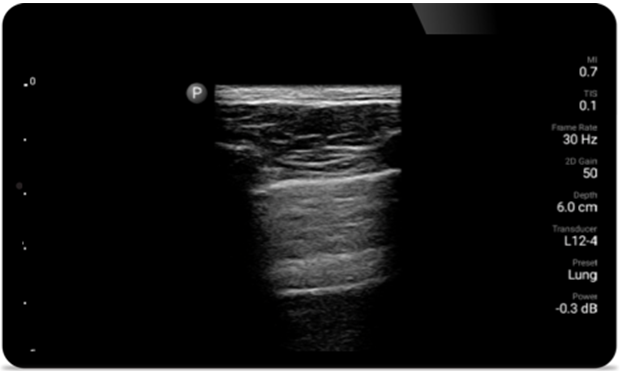

Breathe easier with

Lumify

Lumify can help assess patients faster and improve

accuracy when diagnosing common causes of

dyspnea and other lung conditions.

Lumify L12-4 broadband linear array transducer

• 12 to 4 MHz extended operating frequency range

• Aperture size: 34mm

• 2D, steerable color Doppler, M-mode, advancedXRES and multivariate harmonic imaging, SonoCT

• High resolution imaging for shallow applications: soft tissue, vascular, superficial, musculoskeletal and lung

• Center line marker

• USB-C transducer with replaceable cable